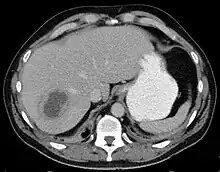

| Liver abscess on axial CT image: a hypodense lesion in the liver with peripherally enhancement. | |

A liver abscess is a mass filled with pus inside the liver.[1] Common causes are abdominal conditions such as appendicitis or diverticulitis due to haematogenous spread through the portal vein.[2] It can also develop as a complication of a liver injury.